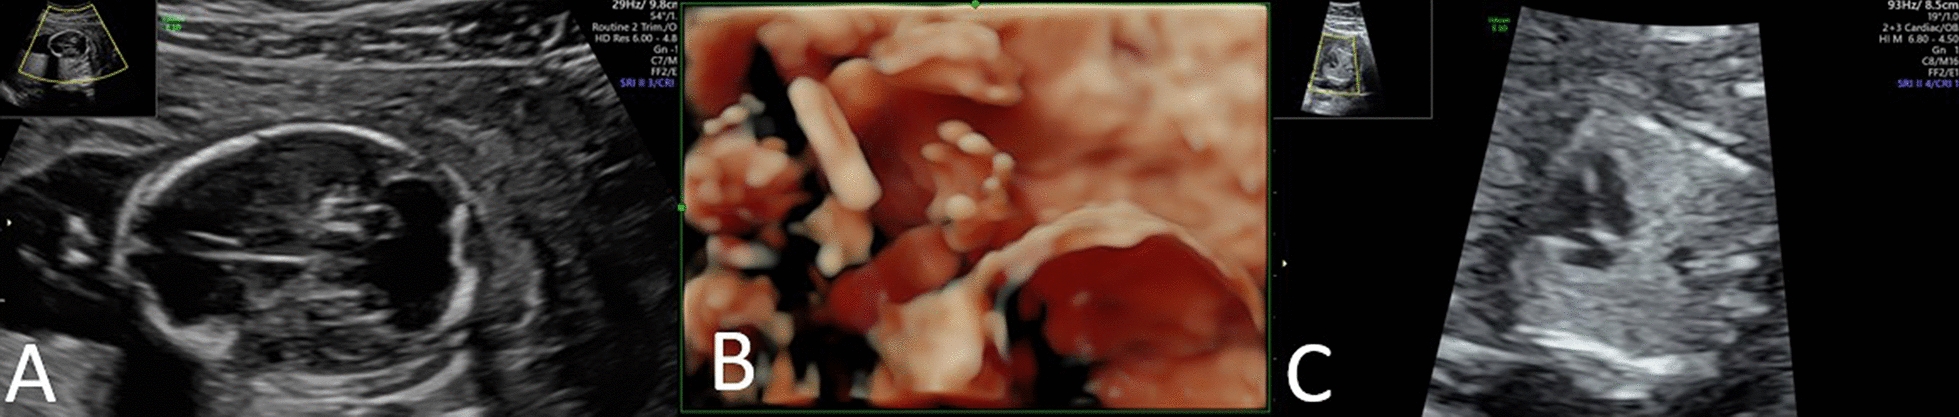

In this case report, we describe a rare prenatal finding of a small marker chromosome. This marker chromosome corresponds to an inverted duplication of the 13q region 13q31.1q34 (or 13q31.1 → qter) with a neocentromere, detected during genetic analysis of a chorionic villus sample in a fetus with multiple congenital anomalies after a normal prenatal screening result by noninvasive prenatal testing.